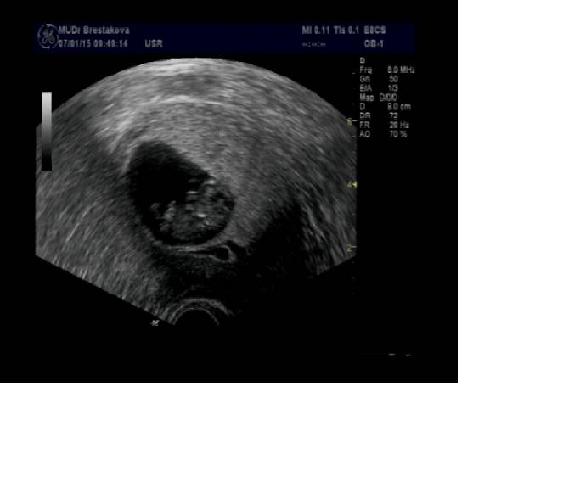

Jinak já dnes byla na kontrole a mimi odpovida 10tt a vse jak ja ma byt, jen neslo moc dobre zachytit na fotku, ale srdicko blikalo, ruce, nohy má, doktorka rikala, ze je spokojena, takze ja taky 🙂 Průkazku jsem uz dostala.